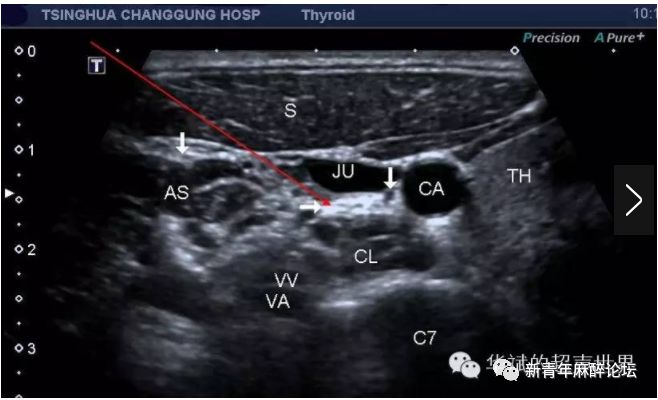

图2超声引导第七颈椎水平超声图像(引自:张华斌华斌的超声世界)

(图2第七颈椎横突水平横断。TH:甲状腺,CL:颈长肌,C7:第六颈椎,CA:颈总动脉,JU:颈内动脉,AT:第6颈椎横突前结节,PT:第6颈椎横突后结节,AS:前斜角肌,S:胸锁乳突肌,VV和VA:椎动脉和椎静脉。左边箭头:膈神经,右边箭头:迷走神经。水平箭头:星状神经节。)

由上图可见,这一断面可以清晰显示位于颈动脉鞘(其内有颈总动脉、颈内静脉和迷走神经)和颈长肌之间的星状神经节(位于颈长肌表面,椎前筋膜深面),呈现为高回声的筛网状结构。同时可见星状神经节周围有许多血管神经结构。

正是由于超声能够清晰分辨星状神经节的结构,因此目前的星状神经节阻滞一般都是在超声引导下施行,能够做大程度地避免并发症的发生,同时由于定位准确,能够利用较少的药量就能达到满意的效果。

超声引导下星状神经节阻滞选择C7横突所示的断面,由外侧入路(即图中红色长箭头所示),药液注射于星状神经节周围。操作前年务必打开超声多普勒或血流确认椎动脉/静脉位置,以免穿刺针刺破椎动静脉造成局部血肿,严重者误入局麻药,药液随椎动脉直接入脑,导致局麻药中毒,抢救非常棘手。成功的星状神经节阻滞后患者会出现典型的Horner征的表现,即:眼睑下垂、面色潮红无汗、瞳孔缩小等。